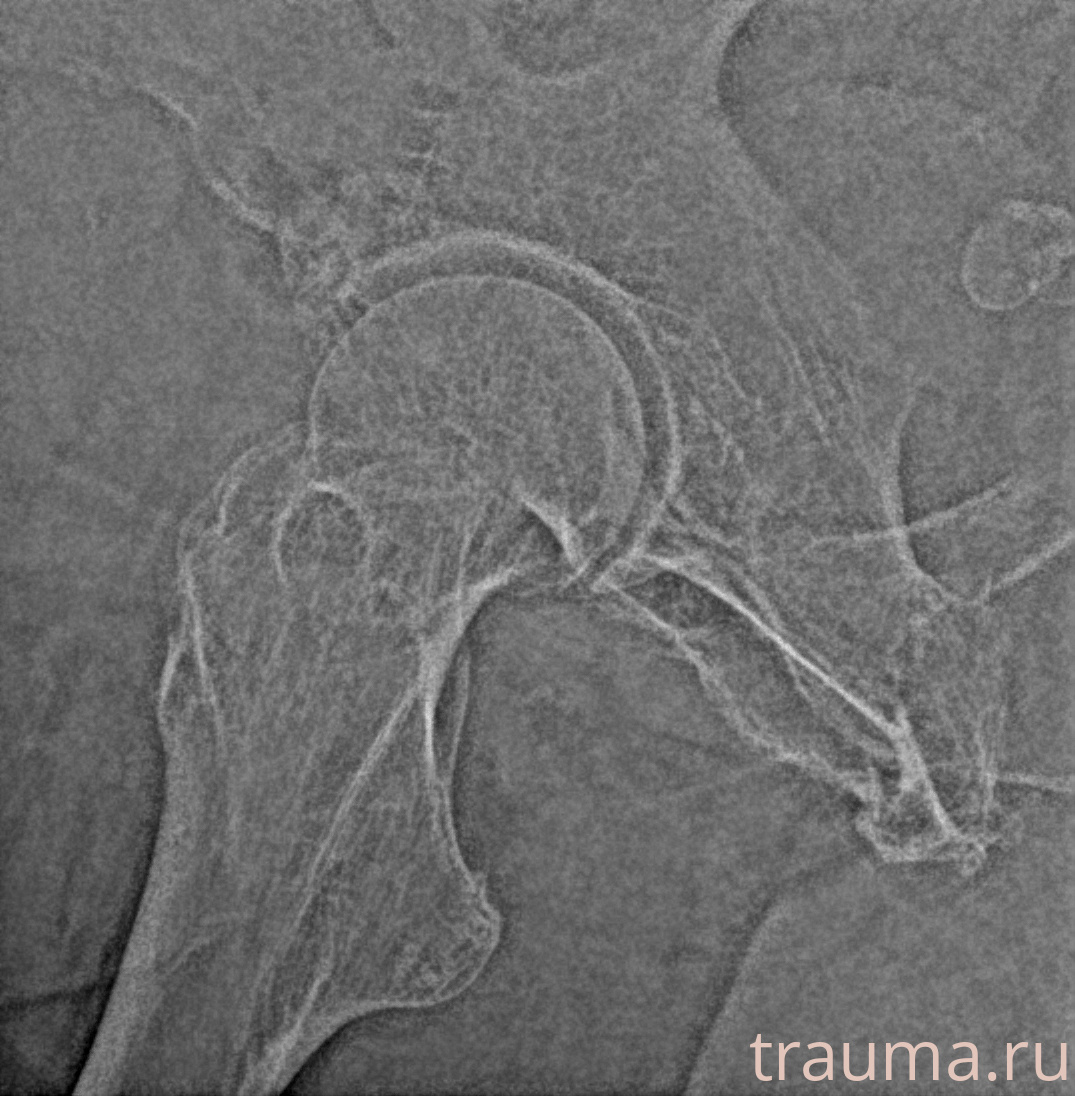

Рентгенограммы

Рентген на дому: по вашему адресу приезжает врач-рентгенолог, травматолог-ортопед с мобильным рентгеновским аппаратом, проводит диагностику травмы или заболевания, делает необходимые рентгенограммы, дает рекомендации по дальнейшему лечению. Получить качественные снимки в домашних условиях возможно благодаря уникальной методике, разработанной МосРентген Центром для института  Склифосовского